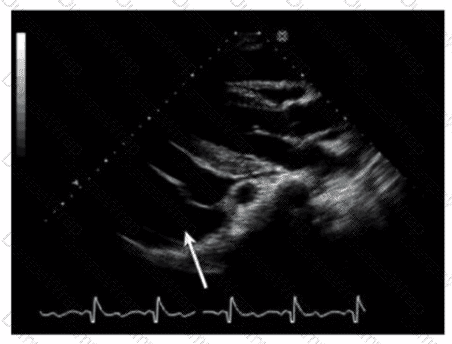

Which anatomic structure is represented by the arrow on this image?

DExplanation:

The echocardiographic image is a four-chamber view focusing on the mitral valve apparatus. The arrow points to the anterior leaflet of the mitral valve, which is typically more prominent, triangular in shape, and located adjacent to the aortic valve in the left ventricular outflow tract region.

The posterior leaflet of the mitral valve is generally smaller, has multiple scallops, and is located posteriorly relative to the anterior leaflet. The septal leaflet is part of the tricuspid valve on the right side of the heart. The "left leaflet" is a non-specific term and not an anatomical descriptor.

This differentiation between anterior and posterior leaflets is important for understanding mitral valve pathology and for interventions such as mitral valve repair. These features are clearly explained in echocardiography texts and ASE valve imaging guidelines【12:ASE Valve Imaging Guidelines†p.180-185】【16:Textbook of Clinical Echocardiography, 6e†p.200-205】.